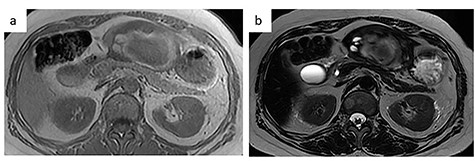

A 56-year-old woman presented to another hospital with acute abdomen. Computed tomography (CT) examination demonstrated a tumor 10 cm in diameter that protruded from the left lateral segment of the liver, with evidence suggestive of rupture of the liver tumor (Fig. 1). Since the patient was in good general condition, she was referred to our hospital for further evaluation. Her blood biochemical parameters when she was referred to our hospital were hemoglobin: 11.6 g/dl, albumin: 3.4 g/dl, γ-globulin: 18.5% and anti-acetylcholine receptor antibody: <0.3 nmol/L. Dynamic CT presented a liver tumor 10 cm in diameter, which was located at the left lateral segment of the liver, with a clear margin. A mass with an irregular margin was also identified in the anterior mediastinum (Fig. 2). On percutaneous angiography, since obvious extravasation of the contrast medium could not be identified, the arteries of the left lateral segment were embolized to prevent re-bleeding. Although a definitive preoperative diagnosis could not be made using magnetic resonance imaging (MRI) (Fig. 3), fluorodeoxyglucose positron emission tomography (FDG) showed increased FDG uptake in both the hepatic and anterior mediastinal tumors (Fig. 4). Although the liver tumor was suspected to be metastasis secondary to a thymoma based on the clinical findings, percutaneous tumor biopsy was performed to confirm the pathological diagnosis. The biopsy suggested malignant T-cell lymphoma or metastatic thymoma. In order to prevent re-rupture of the hepatic tumor, to confirm the pathological diagnosis and to potentially achieve a curative resection, the patient underwent laparoscopic left lateral segmentectomy (Fig. 5). Although the tumor was found to be adherent to the stomach, blunt dissection was possible. In addition, no peritoneal dissemination was detected. The surgical duration was 212 min and estimated blood loss was 50 ml. The liver tumor was pathologically diagnosed as metastatic thymoma type AB (Fig. 6). The patient’s postoperative course was uneventful and she subsequently underwent radical thymectomy 3 months after the liver resection. The thymic tumor was pathologically diagnosed as thymoma type B2. Currently, 30 months after thymectomy, she remains free from tumor recurrence.

MRI. (a) T1-weighted image: low-intensity area suggestive of intratumor hemorrhage. (b) T2-weighted image: the tumor had heterogenous intensity.

In the present case, contrast-enhanced CT demonstrated two-layered enhancement of the liver tumor. Considering the gross findings of the liver tumor, the inner layer consisted of a hematoma, and the outer layer was formed by compression of the tumor into a crescent shape by the intratumor hematoma, as seen on MRI. Since thymomas, including those that metastasize to the liver are soft, they can rupture easily and can be easily compressed by intratumor hematoma.